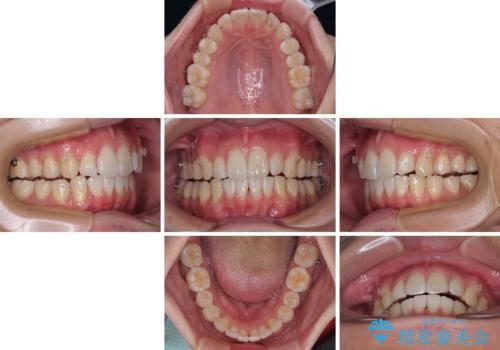

前歯のデコボコをインビザラインで綺麗に改善

- 上下前歯のデコボコとクロスバイトを気にして来院された患者様です。

インビザラインを用い、IPR(歯と歯の間を削る)と歯列全体を拡大させることで、歯並びを整えていくこととしました。

毎日22時間の装着時間を徹底してくださったのですが、左右ともに臼歯が咬合しなくなるという、インビザライン独特の症状が強く長く続いてしまい、終了するまでに長期間を要してしまいました。